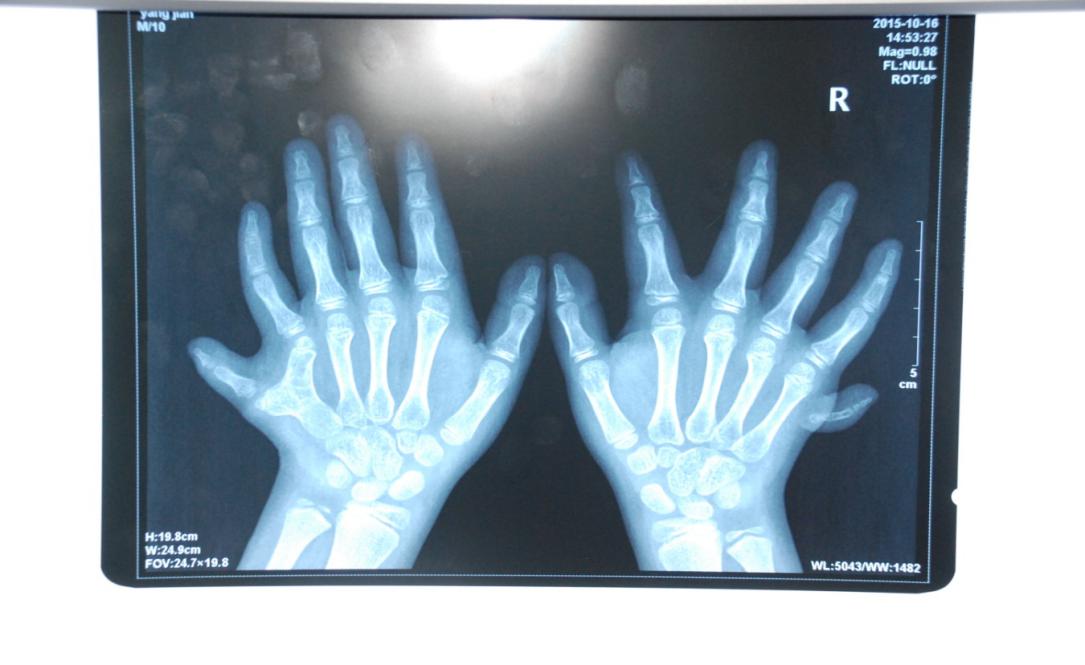

廈門眼科中心小兒眼科修陽暉博士在日常的診療過程中就接診了不少這樣的的特殊家庭,讓其尤為印象深刻的就是一年前接診的BBS綜合征患者。當(dāng)時(shí)來院就診的是一對親兄弟,之前已在多家醫(yī)院做過檢查,因其均有較大散光和斜視,肉眼下眼底檢查未見異常,故外院均診斷為弱視,這也符合眼科門診常規(guī)的診斷邏輯與思維。但由于兄弟倆均有智力發(fā)育遲緩、特殊面容及四肢均有六指和六趾的特異體征引起了修陽暉博士的警覺:會(huì)不會(huì)是一種特殊遺傳性疾病或綜合征?后續(xù)的檢查結(jié)果進(jìn)一步證實(shí)了修陽暉博士的懷疑---患兒均有夜盲,ERG、VEP及OCT檢查顯示雙眼的視網(wǎng)膜神經(jīng)上皮層結(jié)構(gòu)及功能均明顯異常。由于之前未遇到此種病例,修陽暉博士在診斷一欄寫下視網(wǎng)膜色素變性并打上了個(gè)問號,同時(shí)留下了病人的聯(lián)系方式。

BBS綜合征(Bardet-Biedl綜合征)是一種主要累及纖毛結(jié)構(gòu)與功能的罕見常染色體隱性遺傳性疾病。纖毛分布于哺乳動(dòng)物體內(nèi)的大多數(shù)細(xì)胞,它是一種廣泛存在于各種細(xì)胞表面的細(xì)胞器,體型微小但結(jié)構(gòu)復(fù)雜、作用強(qiáng)大,能感知細(xì)胞外機(jī)械和化學(xué)信號變化并協(xié)助其轉(zhuǎn)導(dǎo)到細(xì)胞內(nèi)部從而引起細(xì)胞應(yīng)答。高等動(dòng)物的視覺、觸覺、嗅覺、聽覺的傳遞都依賴于體內(nèi)外正常的纖毛結(jié)構(gòu)和功能。因此BBS綜合征常累及全身多個(gè)系統(tǒng)和器官,在臨床上主要表現(xiàn)為:視網(wǎng)膜色素變性、智力發(fā)育異常、向心性肥胖、多指(趾)、性腺發(fā)育異常、腎臟異常。除此之外還有許多諸如:語言發(fā)育障礙、聽力異常、嗅覺異常、斜視、白內(nèi)障、散光、牙齒發(fā)育異常、短指(趾)、并指(趾)、肝纖維化、糖尿病、高血壓等表現(xiàn)。